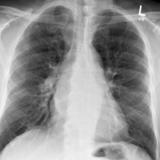

Situs Inversus

Date: 05/11/2004

Views: 5149